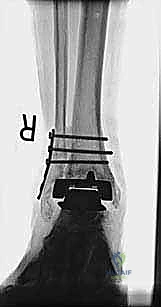

مراجعة مفصل الكاحل الصناعي هي إجراء جراحي ضروري لمعالجة المشاكل التي قد تنشأ بعد الجراحة الأولية، مثل كسور الكعبين أو عدم استقرار المفصل. يتضمن العلاج التشخيص الدقيق عبر الأشعة السينية والتصوير المقطعي، يليه التدخل الجراحي لتثبيت الكسور واستعادة وظيفة الكاحل، مع التركيز على التعافي المبكر.

تُعد جراحة مراجعة مفصل الكاحل الصناعي (Revision Total Ankle Replacement) من الإجراءات الجراحية المتقدمة والبالغة الدقة في عالم جراحة العظام الحديثة. لا تقتصر هذه الجراحة على مجرد استبدال مفصل تالف بآخر جديد، بل هي عملية إنقاذ معقدة للغاية تهدف إلى معالجة المشاكل الميكانيكية والبيولوجية التي تنشأ بعد الجراحة الأولية. من أبرز هذه المشاكل: الفشل الميكانيكي للمفصل، تحلل العظام (Osteolysis)، أو حدوث كسور معقدة في الكعبين (Malleolar Fractures) المحيطة بالمفصل الصناعي. يتطلب هذا الإجراء تقييماً سريرياً وشعاعياً دقيقاً يشمل التصوير المقطعي ثلاثي الأبعاد والأشعة السينية، يليه تدخل جراحي دقيق لاستعادة التوازن الحيوي والميكانيكي للكاحل والحفاظ على الطرف من البتر أو الدمج.

- الأشعة السينية مع تحميل الوزن (Weight-bearing X-rays): لتقييم الزوايا الميكانيكية وتحديد مدى هبوط المفصل أو وجود كسور في الكعب.

كسور الكعبين (Malleolar Fractures) المصاحبة للمفصل الصناعي

من أعقد التحديات التي تواجه جراحي العظام هي حدوث كسور في الكعب الداخلي (Medial Malleolus) أو الخارجي (Lateral Malleolus) في وجود مفصل صناعي. تحدث هذه الكسور لعدة أسباب:

1. ترقق العظام: حول المفصل الصناعي نتيجة لعدم استخدام الطرف بشكل طبيعي (Stress Shielding).

2. الاصطدام الميكانيكي (Impingement): إذا كان حجم المفصل الصناعي أكبر من اللازم، فقد يضغط على الكعبين من الداخل ويؤدي لكسرهما بمرور الوقت.

3. الإصابات المباشرة: مثل السقوط أو التواء الكاحل.

علاج هذه الكسور يتطلب مهارة فائقة من الدكتور محمد هطيف، حيث يتم استخدام تقنيات الجراحة الميكروسكوبية وتثبيت الكسور باستخدام صفائح معدنية دقيقة ومسامير (Locking Plates) دون المساس بثبات المفصل الصناعي، أو يتم دمج علاج الكسر ضمن عملية مراجعة المفصل الكلية إذا كان المفصل نفسه تالفاً.

يتم إدخال المفصل الجديد المخصص للمراجعة، والذي يحتوي غالباً على سيقان (Stems) تدخل عميقاً في عظمة الساق وعظمة الكاحل لضمان الثبات الميكانيكي. في حال وجود كسور في الكعب، يتم تثبيتها في هذه المرحلة.